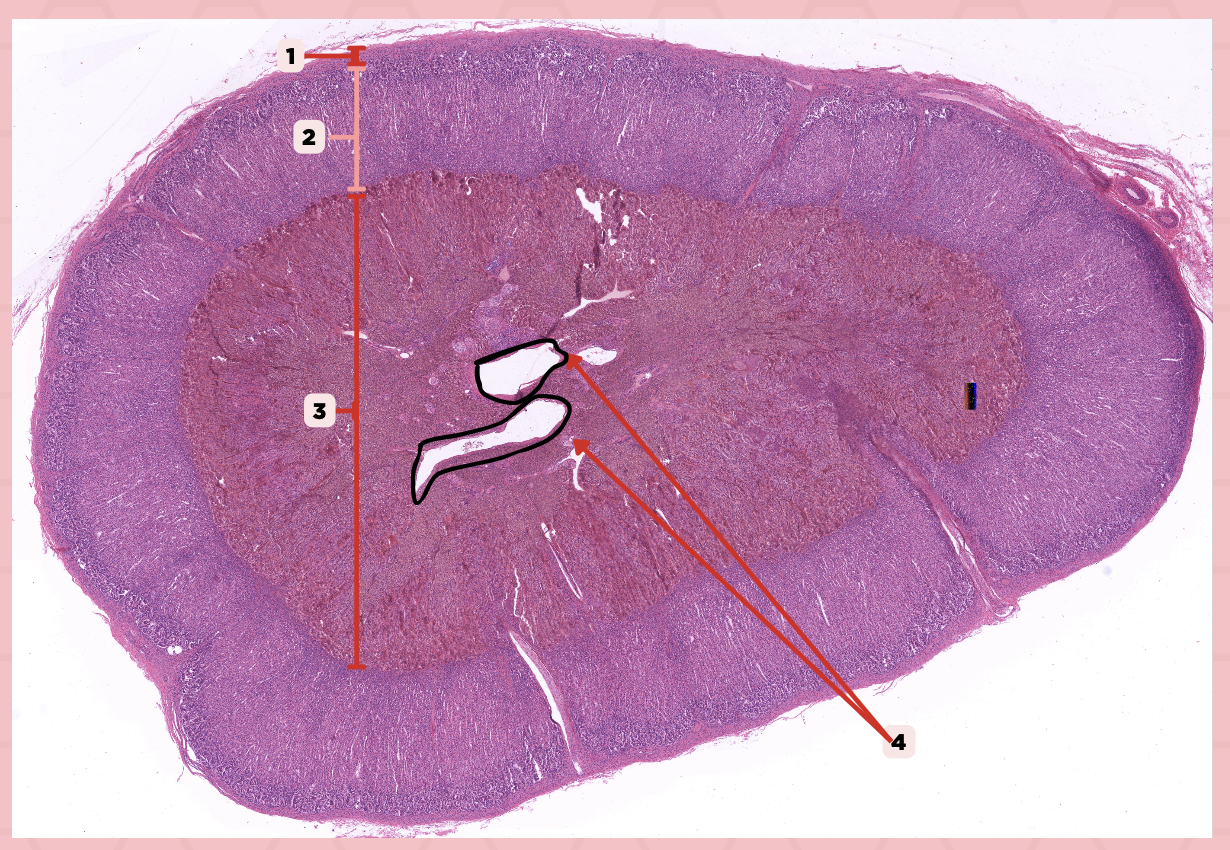

Identify the specimen.

Anterior Lobe

Identify the structure labeled as 1.

Posterior Lobe

Identify the structure labeled as 2.

Intermediate Lobe

Identify the structure labeled as 3.

Pars Tuberalis

Identify the structure labeled as 4.

Pituitary Stalk

Identify the structure labeled as 5.